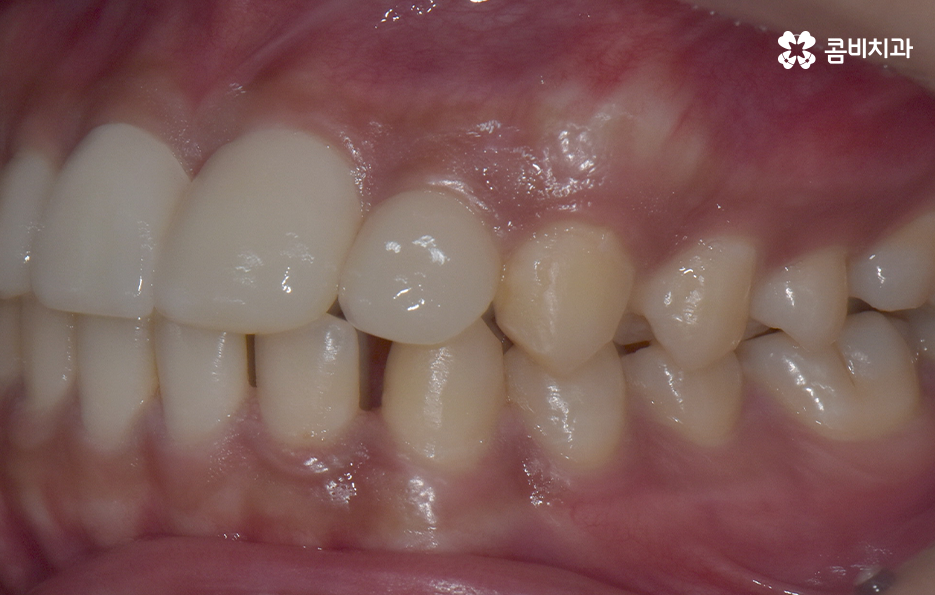

과잉치 중에서는 어떤 치아가 과잉치인지 구분이 어려울 정도로 일반적인 정상 치아의 크기와 비슷한 크기와 형태를 띄는 경우도 있는 반면에 위 사진의 케이스는 첫번째 앞니와 앞니 사이에 유독 작은 왜소치가 있는 형태이기 때문에 치아의 기능적인 문제 보다는 심미적인 개선을 필요했던 케이스로 볼 수 있어요

그나마 다행인 점은 앞니만교정을 하더라도 치아의 교합이나 골격적인 부분, 얼굴형 등에 있어서 큰 지장은 없던 경우였는데요. 물론 아랫니가 다소 벌어져 있기 때문에 전체교정을 하면 더 좋은 결과를 얻을 수 있었겠지만 환자분의 니즈에 있어서 앞니만교정을 빠르게 원했던 사례이기 때문에 앞니 부분의 과잉치 발치 후 앞니만교정을 부분적으로 진행했어요

과잉치로 인해서 치아 배열이 전체적으로 불규칙해지는 경우도 있고 돌출입의 형태로 나타는 경우도 있지만 다행이도 입술라인이나 얼굴형에 있어서 돌출은 크지 않은 상태였다는 점도 앞니만교정을 해도 어느정도 좋은 결과를 낼 수 있던 케이스로 볼 수 있어요

과잉치로 인해 말그대로 치아의 정상 범위 이상으로 치아가 배열되기 때문에 다른 치아의 배열에도 악영향을 주는 경우가 많지만 위 환자분의 케이스의 경우에는 치열 자체는 전체적으로 가지런한 편이라는 점과 특히 턱뼈가 넓은 편이라는 점에서 전체교정을 하지 않았어도 환자분이 원하는 치료의 목표는 달성할 수 있었어요